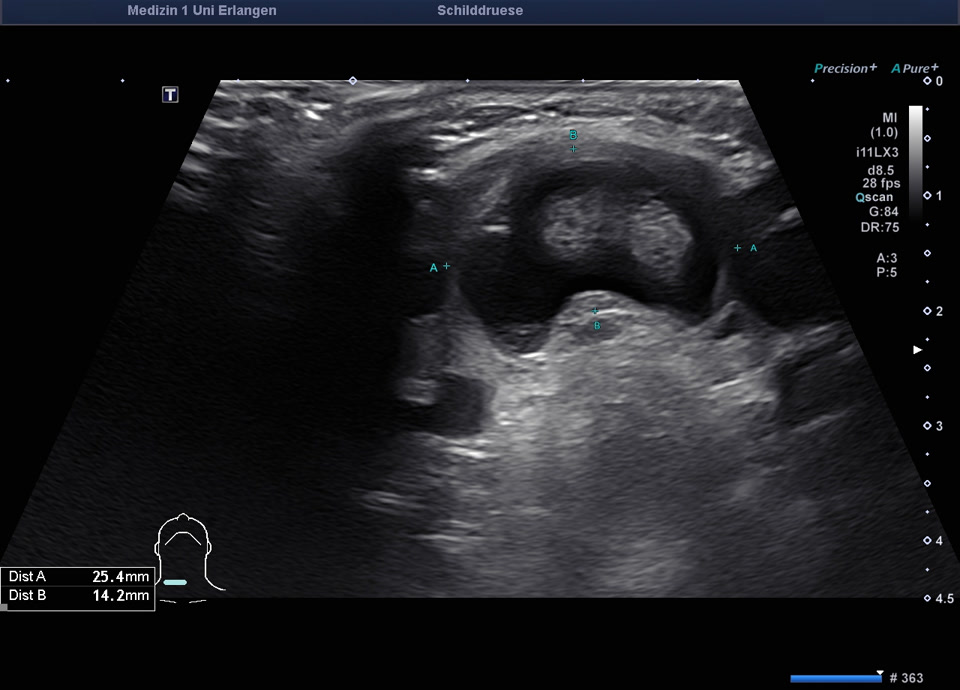

78-jähriger Patient mit Zufallsbefund einer hypodensen Schilddrüsenläsion im Rahmen eines Kardio-CTs vor geplanter Aortenklappenoperation. In der sonographischen Abklärung zeigte sich eine normal große Schilddrüse mit einem 2 cm echoarmen Knoten (EU-TIRADS 4), farbdopplersonographisch ohne relevante intranoduläre Durchblutung. Die Elastometrie zeigte eine erhöhte Gewebesteifigkeit. Der TSH-Wert lag im Normbereich, klinisch bestanden keine Hinweise auf eine Schilddrüsenerkrankung. Es erfolgte eine ultraschallgesteuerte Stanzbiopsie sowie eine Feinnadelpunktion mit zytologischer Aufarbeitung (Zytospin). Histologisch ergab sich ein follikulärer Knoten. Kommentar des Pathologen: anhand der Biopsie kann eine follikuläre Neoplasie nicht sicher von einem autonomen Adenom unterschieden werden. Zur funktionellen Abklärung (zum Nachweis eines autonomes Adenom) sollte eine Schilddrüsenszintigrafie erfolgen. Aufgrund der vorausgegangenen Kontrastmittelgabe (Kardio-CT) ist eine Schilddrüsenszintigrafie erst nach ≥8 Wochen möglich. Vorrangig erfolgt zunächst die Behandlung der hochgradigen Aortenstenose. Nach Durchführung der Szintigrafie ohne Nachweis eines Adenoms sollte aufgrund des Risikos einer follikulären Neoplasie eine operative Abklärung (diagnostische Hemithyreodektomie) erwogen werden. Alternativ sind sonographische Verlaufskontrollen nach 6 und 12 Monaten möglich.